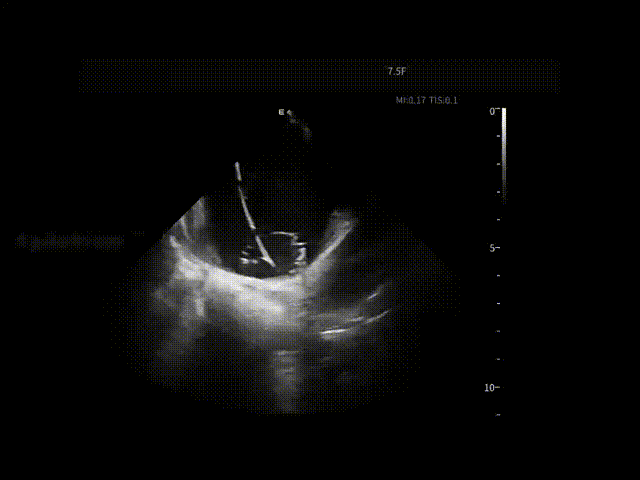

消融开始前,团队将ICE切换至PFA预设成像模式,以获得更贴合脉冲消融需求的术中影像。随着PulseSelect™ 脉冲消融导管逐步靠近肺静脉口及前庭区域,相关解剖边界在ICE下逐渐清晰呈现,为后续贴靠判断提供直观参考。

张曦教授将ICE导管置于右心房作为稳定观察点,在ICE实时影像引导下,PulseSelect™ 导管安全进入左心房,依次完成双侧肺静脉隔离,并进一步实施上腔静脉隔离。

在肺静脉隔离及左房后壁相关操作过程中,ICE持续显示消融导管与心房组织之间的空间关系与贴靠状态,使每一次能量释放都建立在明确的影像反馈之上,减少反复调整,提升操作连贯性。

房间隔穿刺

导管形变与贴靠-LA后壁

导管形变与贴靠-LIPV

导管形变与贴靠-LSPV

导管形变与贴靠-RIPV

导管形变与贴靠-RSPV

LPV口部消融

LPV前庭消融